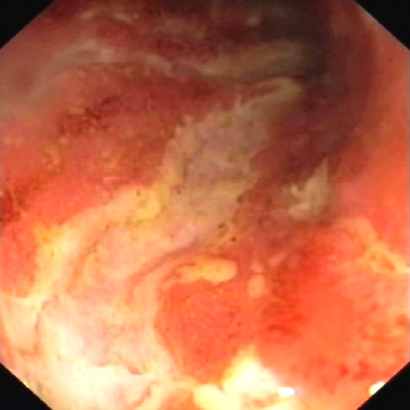

Lors de ces examens d’endoscopies, des lésions endoscopiques évocatrices de maladie de Crohn peuvent être visibles (Figure n°1 et 2) : des ulcérations apthoïdes, des ulcérations en carte de géographie, des ulcérations en rails.

Figures n° 2 et 3 : Ulcérations du colon dans la maladie de Crohn

(Source Gastrolab et Atlas Atlanta)

Mais attention, si ces lésions sont évocatrices elles ne signent pas obligatoirement le diagnostic de maladie de Crohn car elles ne sont pas spécifiques et peuvent se voir au cours des colites bactériennes. Nous verrons par la suite la difficulté de diagnostic avec ces atteintes infectieuses. Un caractère plus spécifique de la maladie de Crohn est le caractère discontinu et multi-segmentaire des lésions endoscopiques.